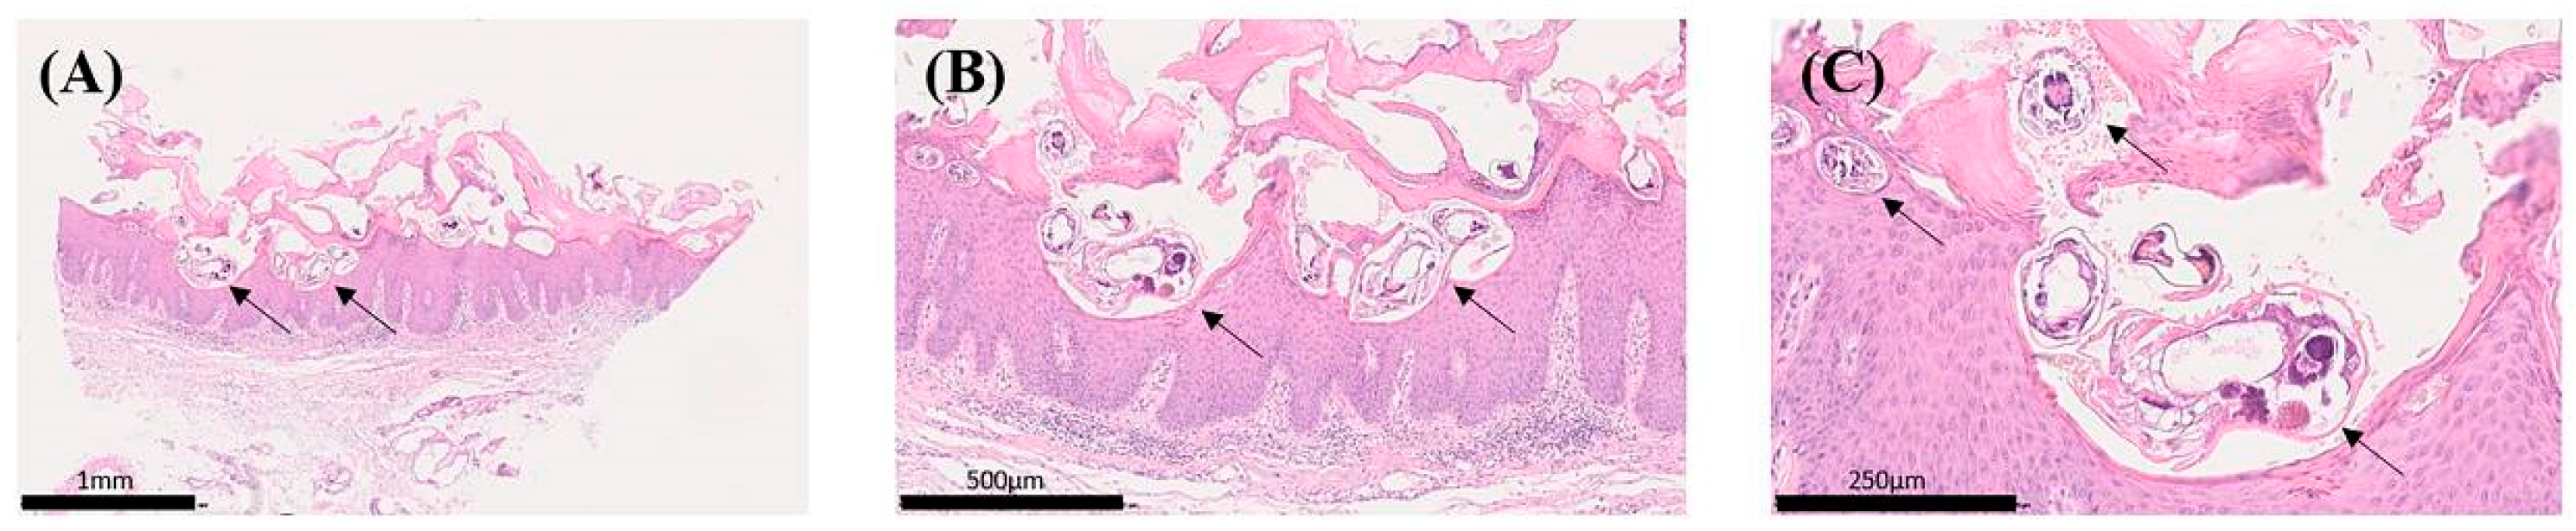

4.2. Acquisition and Preparation of Skin Tissue Specimens